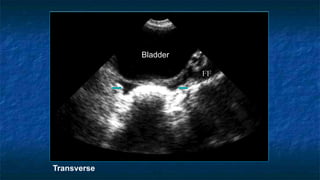

3)FAST: Pelvis exam

 Pelvis: Longitudinally and Transvers Axis.

 Probe placed

 Transeversally then Longitudinally

 Midline 2 cm superior to the symphysis pubis

 “aimed” caudally into the pelvis (prostate )

 Probe facing

 Toward patient’s head and right side.

 Best with some urine in bladder(acoustic window)

 Evaluating

 Bladder ,Uterus in female ,and Prostate in

male

 The potential spaces are Pouch of

Douglas (Cul de sac ) in female and

retrovesicle space in male

FAST: Pelvis exam

 Pelvis: Transverse Axis

 Normal Anatomy

 Evaluating Bladder

 Well cirucumscribed

 Contains fluid that

appears anechoic

Transverse

FAST: Pelvis exam - Pathology

Bladder

FF

3)FAST: Pelvis exam Pelvis: Longitudinally and Transvers Axis.  Probe placed  Transeversally then Longitudinally  Midline 2 cm superior to the symphysis pubis  “aimed” caudally into the pelvis (prostate )  Probe facing  Toward patient’s head and right side.  Best with some urine in bladder(acoustic window)  Evaluating  Bladder ,Uterus in female ,and Prostate in male  The potential spaces are Pouch of Douglas (Cul de sac ) in female and retrovesicle space in male

FAST: Pelvis exam Pelvis: Transverse Axis  Normal Anatomy  Evaluating Bladder  Well cirucumscribed  Contains fluid that appears anechoic Transverse Anterior Right Left Posterior

FAST: Pelvis exam- Pathology Transverse